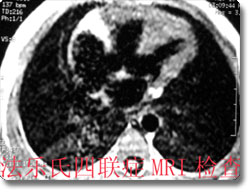

先天性心血管疾病的影像诊断

本科室有丰富的先天性心脏病的诊断经验和手段,通过心血管造影、MRI等方法,可以对先天性心脏病法乐氏四联症、三联症、三尖瓣异常、动脉导管未闭、房(室)间隔缺损、大血管位置及引流异常等在术前作出比较准确的影像诊断和评估,为临床手术治疗提供可靠的诊断依据,极大的提高了先天性心脏病的诊治水平,对间隔缺损和动脉导管未闭患者还可进行介入性微创治疗,在国内处于领先地位。